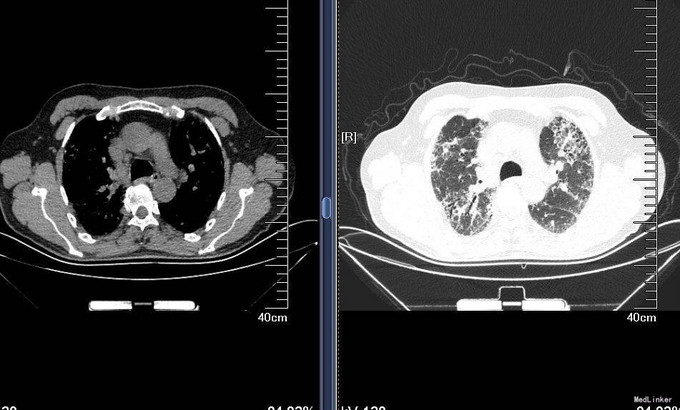

查体:T36.5℃,P 80次/分,R 18次/分,BP 120/80mmHg,神清语明,查体合作,周身皮肤无黄染及出血点。巩膜无黄染,结膜无苍白,球结膜无水肿,口唇无发绀,颈静脉无充盈,颈部浅表淋巴结未触及。双肺呼吸音粗,未闻及干湿性啰音,心音钝,律齐,各瓣膜听诊区未闻及病理性杂音。腹平软,无压痛,无反跳痛及肌紧张,未触及包块。肝肋下未触及,双肾区无扣痛,移动性浊音阴性。双下肢无水肿。 入院后完善肝肾功离子,血气分析,血常规,CRP,支原体抗体,肺通气功能,弥散功能等检查,检验回报:血常规:白细胞计数 9.710^9/L;中性粒细胞百分比 46.8%;红细胞计数 4.6810^12/L;血红蛋白 148g/L;血小板计数 21310^9/L;CRP:C-反应蛋白 <3.28mg/L;肺炎支原体抗体:肺炎支原体抗体 阴性(-); 肺通气功能:FEV1/FVC:90,%Pre:78%,混合性通气功能障碍,以限制为主;支气管舒张试验试验:支气管舒张试验阴性,FEV1改善率1%,增加30ml;弥散功能:总弥散量中度下降,单位弥散量正常;胸部HRCT:双肺弥漫性间质性肺炎。 双侧胸膜局部增厚。